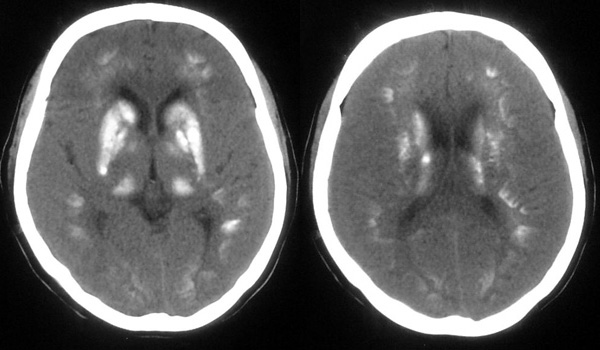

患者,女,49岁,头痛数年,有癫痫病史,无外伤史。

甲状旁腺低下:颅脑 ct 可见以基底节为中心的双侧对称性、多发性、多形性脑钙化的特点。除苍白球外,可广泛分布于壳核、尾状核、小脑齿状核、丘核、内囊及脑皮质、白质等处。